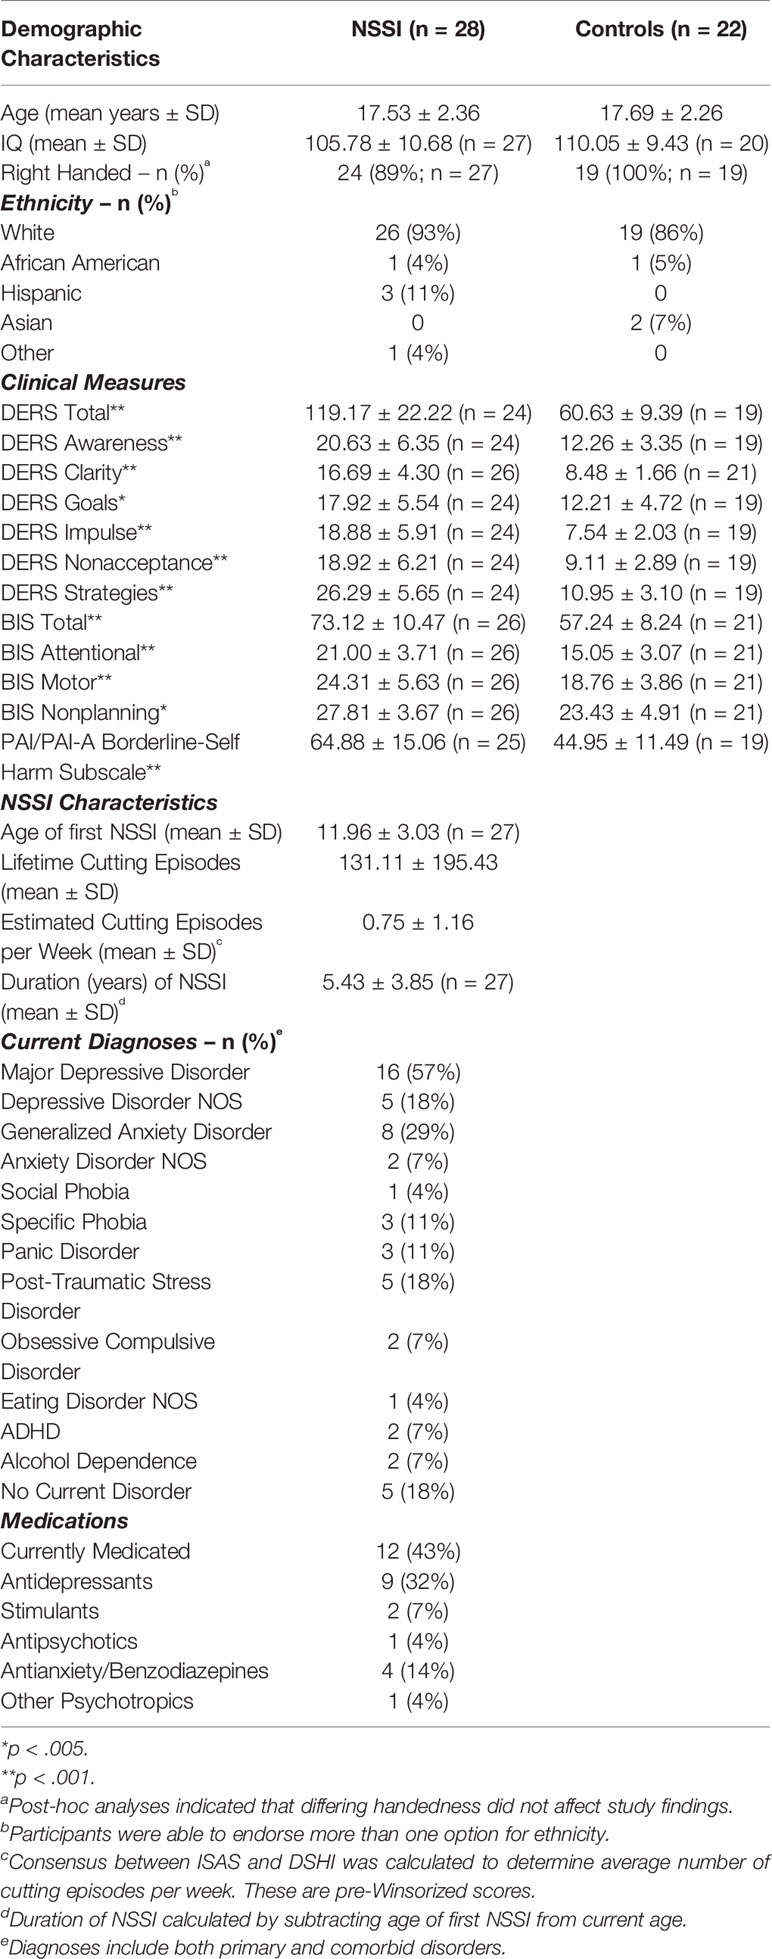

Overall, 29 NSSI and 22 HC completed all study procedures. After one subject was excluded due to poor dMRI data quality, data from 28 NSSI and 22 HC participants were used for the final analyses. The number of NSSI participants who completed each of the clinical measures for this study varied. Further demographic and clinical characteristics for the sample can be found in Table 1.

dMRI

The whole brain group comparison analyses revealed several areas that showed significantly lower GFA in the NSSI group when compared to the HC group at a corrected p < .01 (corrected through permutation testing within TFCE as described in 39). In addition to the cingulum and uncinate fasciculus as predicted, these areas also included bilateral superior and inferior longitudinal fasciculi, anterior thalamic radiation, callosal body, and corticospinal tract. Figure 2 depicts the locations of these group differences.

Figure 2 Group Differences in GFA: Controls > NSSI. White matter tracts in red show where controls have significantly greater GFA than NSSI. This is overlaid on the mean GFA skeleton (light green). Findings were significant at p < .01.

Lower GFA of the left and right uncinate fasciculus was associated with higher total scores on the attentional subscale of the BIS. A correlation matrix can be found in Table 2, which includes comparisons that were significant at an uncorrected p < .05. For the left and right cingulum, there were no significant associations with measures of self-regulation (DERS and BIS). A correlation matrix can be found in Table 3. Finally, lower GFA of the left cingulum was associated with a longer duration of NSSI. There were no significant correlations between other severity indices (e.g., average number of episodes) and GFA. These in addition to results from other comparisons can be found in the correlation matrix in Table 4.